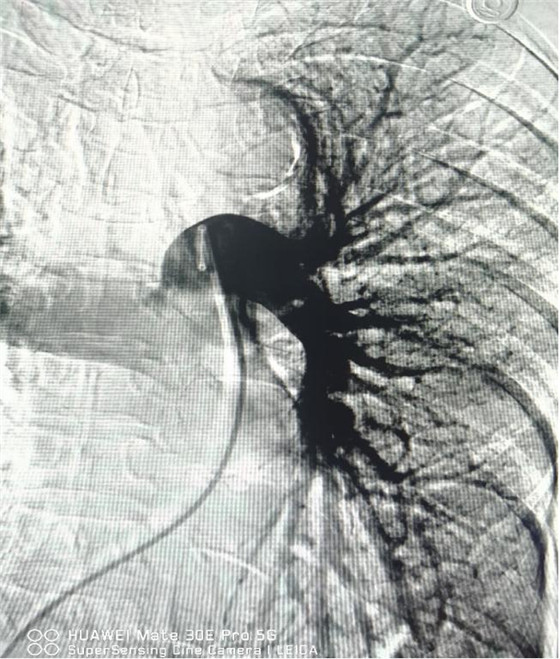

術(shù)后肺動(dòng)脈血流恢復(fù)通暢

經(jīng)綜合評(píng)估并與家屬充分溝通后,局麻下行肺動(dòng)脈造影,提示左肺動(dòng)脈主干及左肺下葉動(dòng)脈閉塞,立即予以經(jīng)皮肺動(dòng)脈栓塞導(dǎo)管介入碎栓溶栓術(shù)。在心內(nèi)科韋鋒主任、郭良玉主治醫(yī)師及成婷護(hù)師的默契配合下,爭(zhēng)分奪秒順利完成手術(shù)。術(shù)后即刻復(fù)查肺動(dòng)脈造影示左肺動(dòng)脈主干及左肺下葉動(dòng)脈恢復(fù)血流,生命體征穩(wěn)定,指脈氧恢復(fù)至100%。經(jīng)過(guò)精心治療與護(hù)理,目前患者已康復(fù)出院。